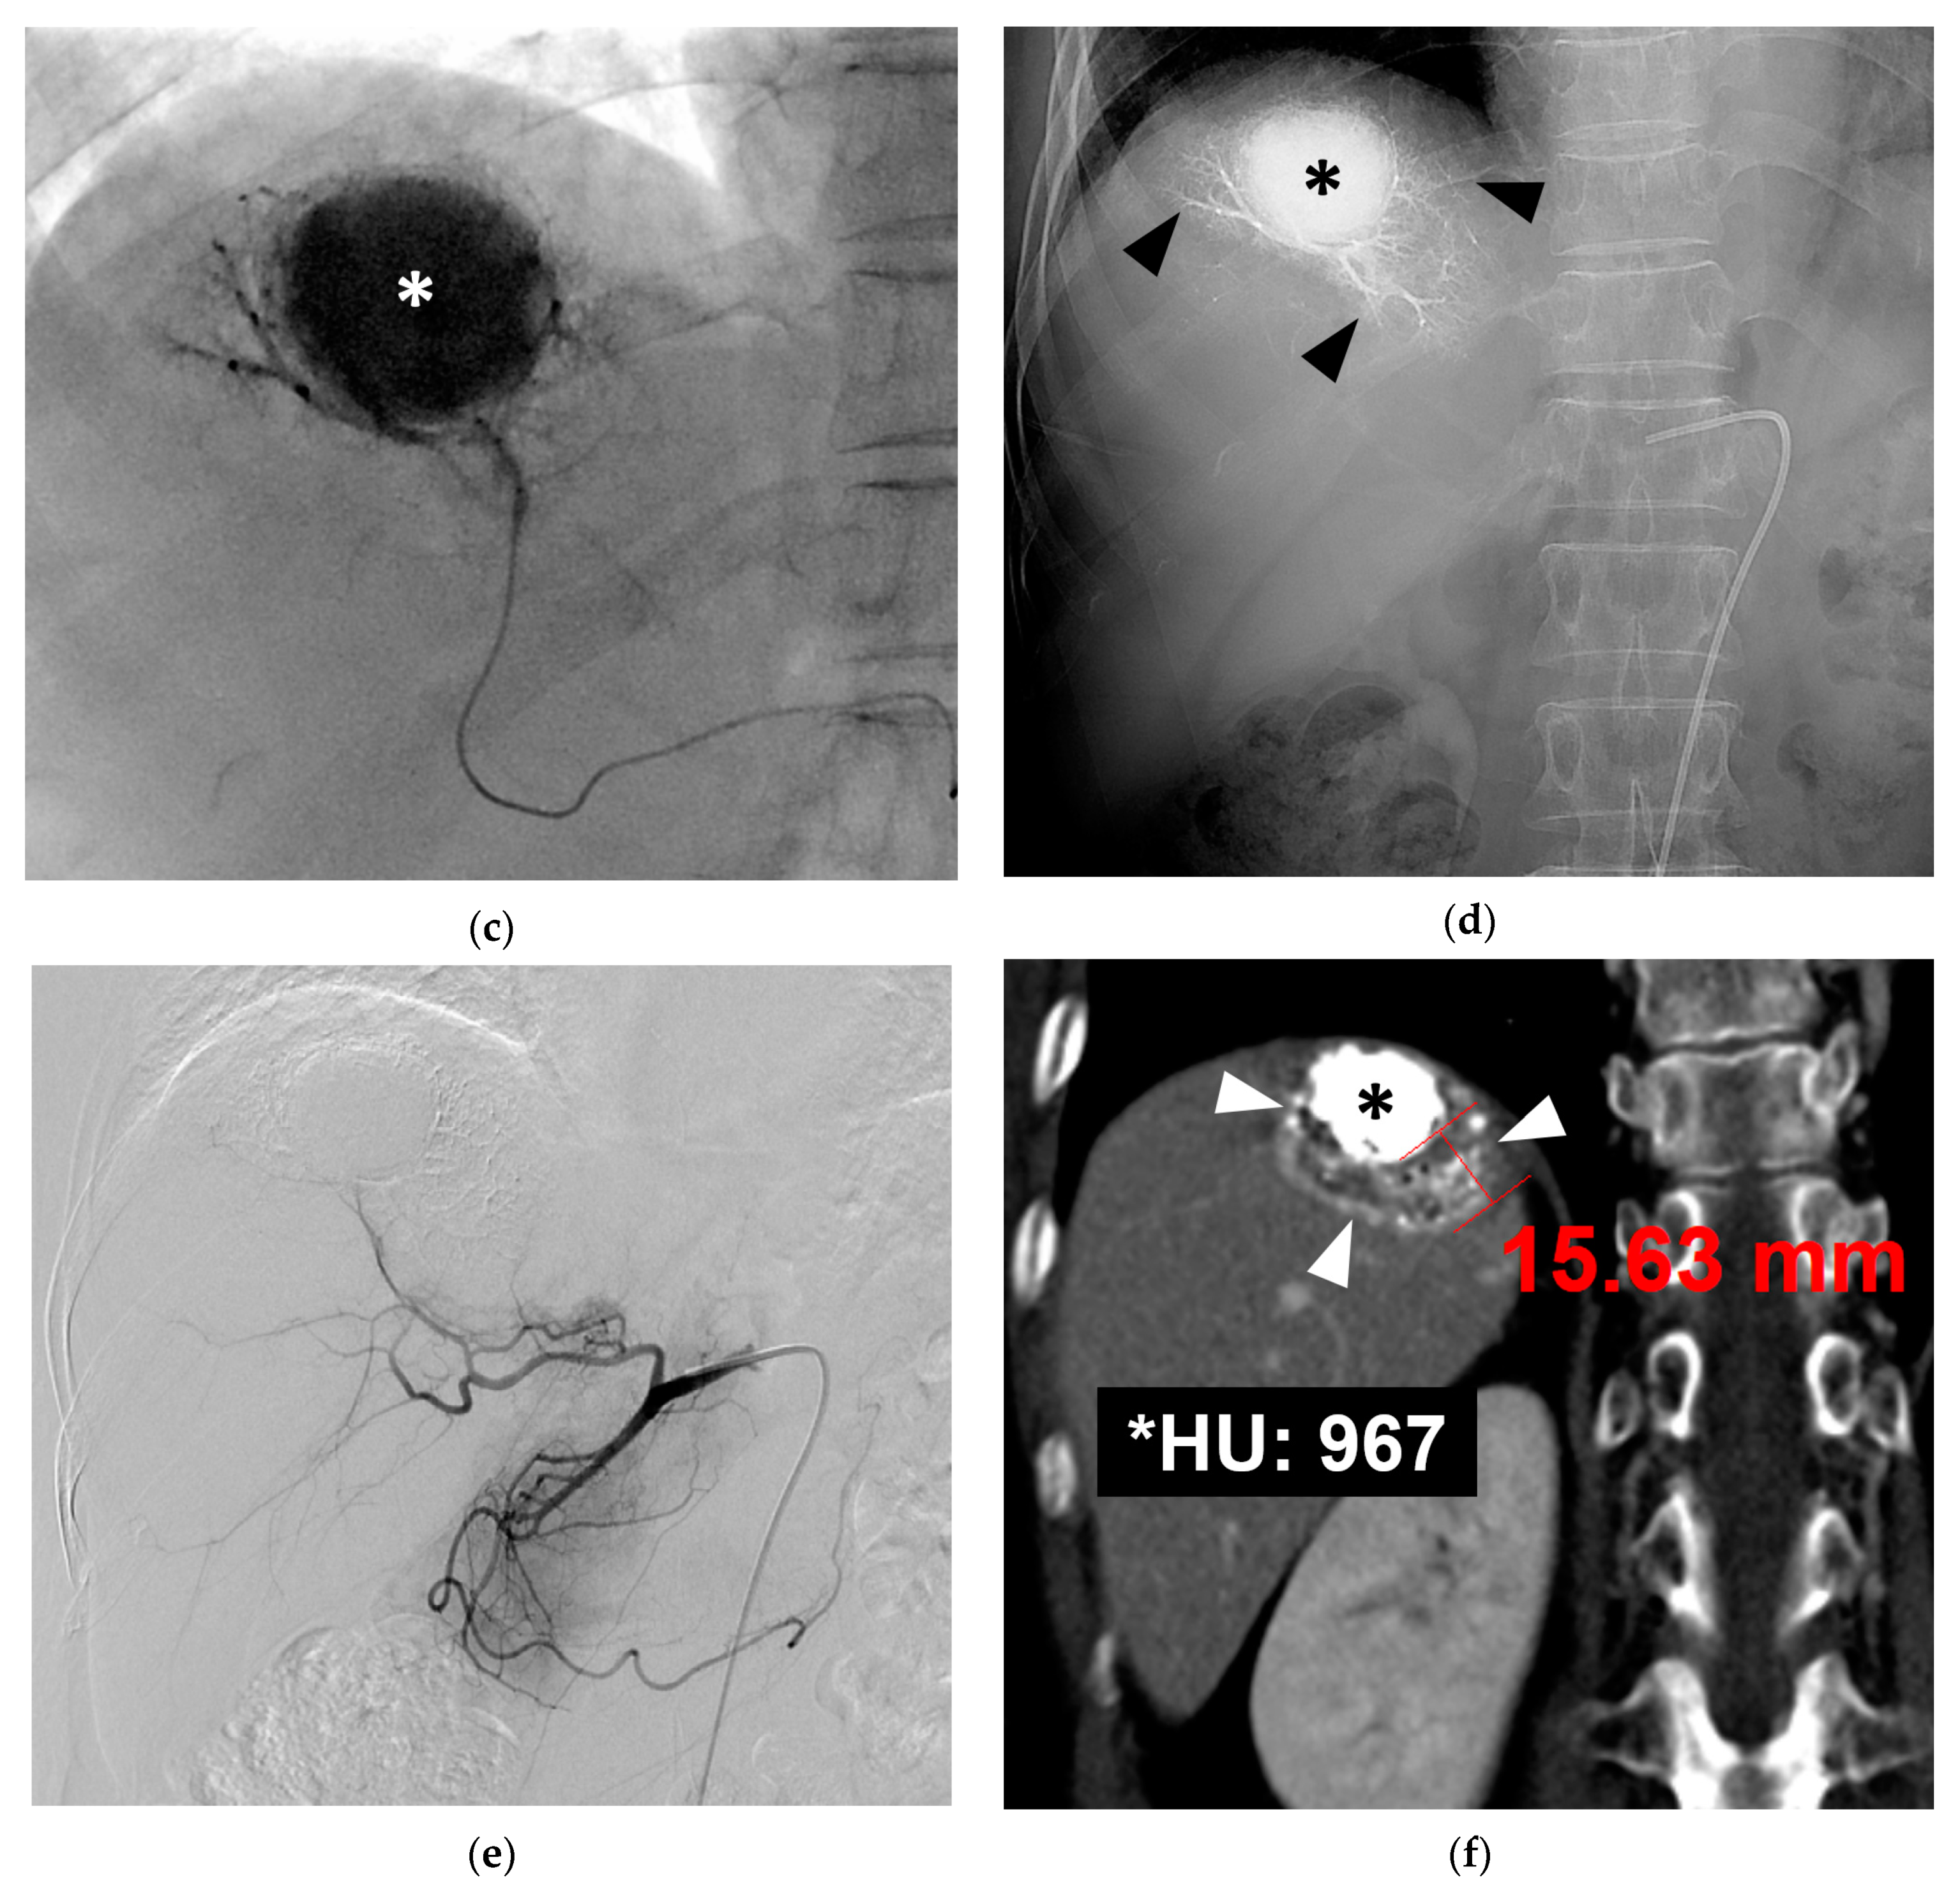

3.1. B-TACE Procedure and Complications